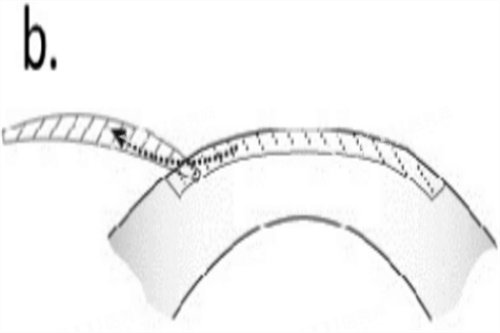

半飞秒手术:个性化定制

半飞秒技术结合飞秒激光制瓣与准分子激光切削,价格更具弹性。标准半飞秒手术约8800-12800元,个性化方案(如德国蔡司设备)则达12800-15800元。青岛分院数据显示,部分患者选择高端套餐后总费用接近18000元。